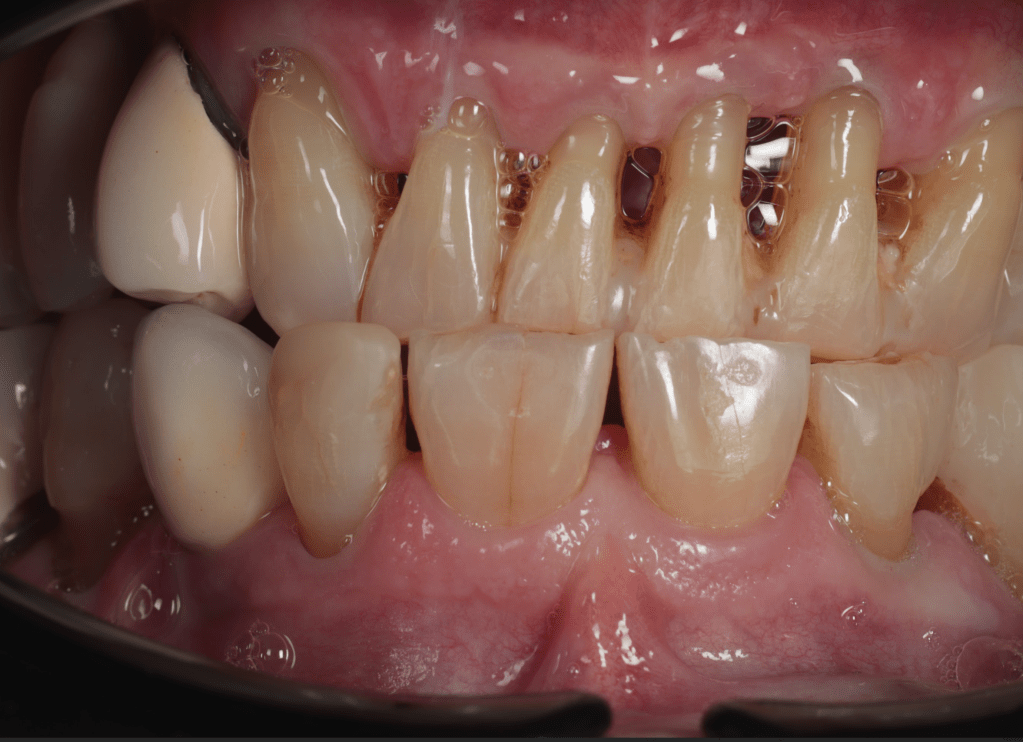

Reco pared vesticular